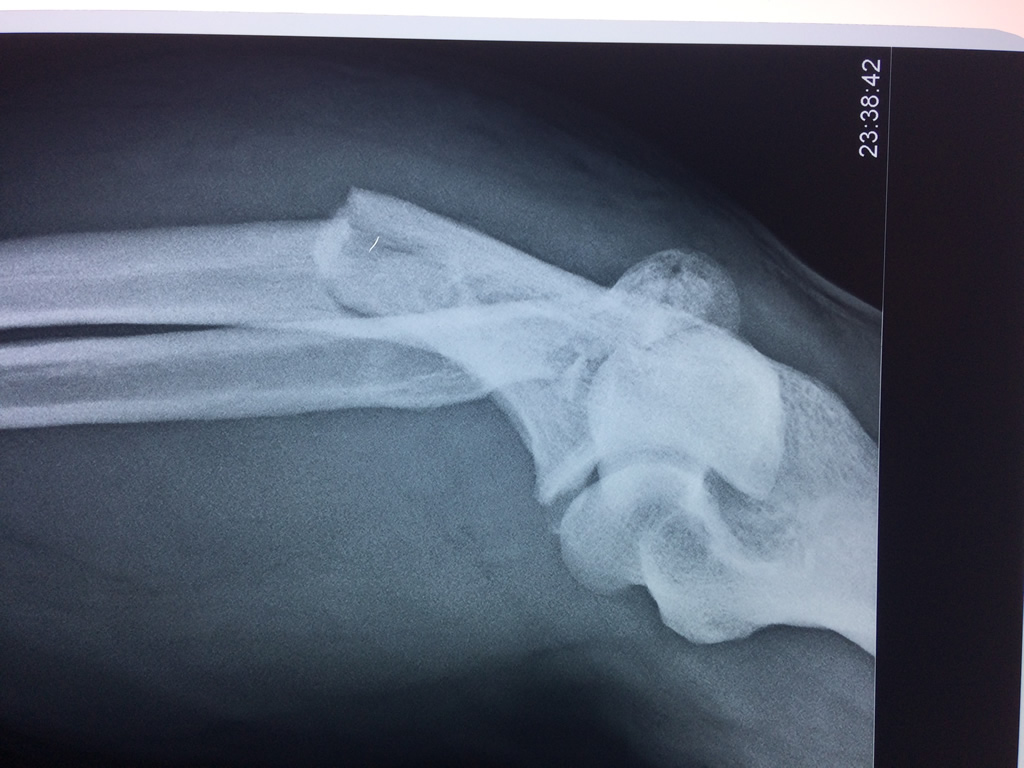

En anatomía humana, la articulación del codo es la que une el brazo con el antebrazo, conectando la parte distal del hueso húmero con los extremos proximales de los huesos cúbito y radio.

La articulación principal que constituye el codo se denomina humero radio-cubital y puede dividirse en dos partes bien diferenciadas, la articulación humero-radial y la humero-cubital.

Por otra parte el cúbito y el radio forman también una articulación entre si en las proximidades del codo, la cual se denomina articulación radio-cubital proximal.

Los extremos óseos se conectan entre si por un conjunto de ligamentos que contribuyen a su fijación y están rodeado por una estructura común que se llama cápsula articular, en cuyo interior se encuentra el líquido sinovial.